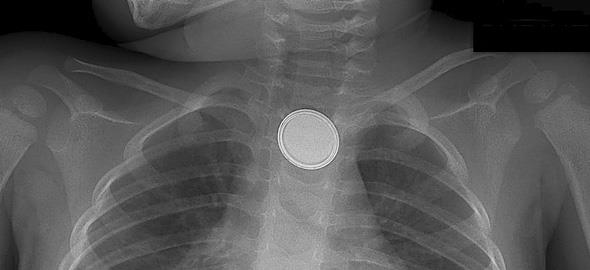

Η δίχρονη κόρη του Asan, Francesca, κατάπιε μια μικρή στρογγυλή μπαταρία. Ωστόσο, ο θάνατός της δεν προκλήθηκε από πνιγμό. Αφού κατάπιε την μπαταρία, χωρίς να το καταλάβουν οι γονείς της, η Francesca Asan υπέστη εσωτερική αιμορραγία, μόλις η μπαταρία ήρθε σε επαφή με τα σωματικά υγρά της μικρής.

«Όταν μάθαμε ότι ήταν μια μπαταρία-κουμπί, πήγα κατ’ ευθείαν στο ντουλάπι που φυλάμε τα 3D γυαλιά της τηλεόρασης. Ήταν μία απ’ τις επιπλέον μπαταρίες, που βρισκόταν σε διαφορετικό κουτί απ’ αυτό των γυαλιών».